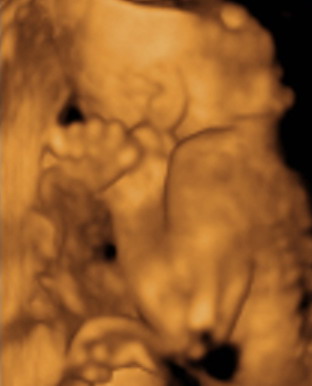

POcak fotó: mi itthon csináltunk, az is tökjó lett. Én ugye lenni kisbálna, így nem akartam volna művészi képeket csinálni magamról... Most se kívánkozik

Igaz Alex pocakról nincsen annyi képem, mint Hannáról... most valahogy Hanna és a meló elvitte azt a maradék erőmet is, hogy a képeket megcsináltassam Ádámmal. Szimplán nem jutott eszembe.